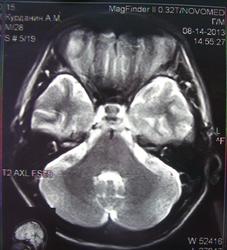

При изучении МРТ снимков головного мозга невролог указала на наличие маленьких очажков на коре головного мозга, порекомендовав обратиться за лечением к нейрохирургам. Голова также продолжает болеть, еще стали кисти рук неметь и прочие симптомы. Можете ли вы указать, имеются ли эти маленькие очажки на коре головного мозга и где именно?

Алексей, очагов достоверно не вижу, а вот на верхнечелюстную пазуху нужно обратить внимание-есть ее воспалительные изменения в виде утолщения слизистой.